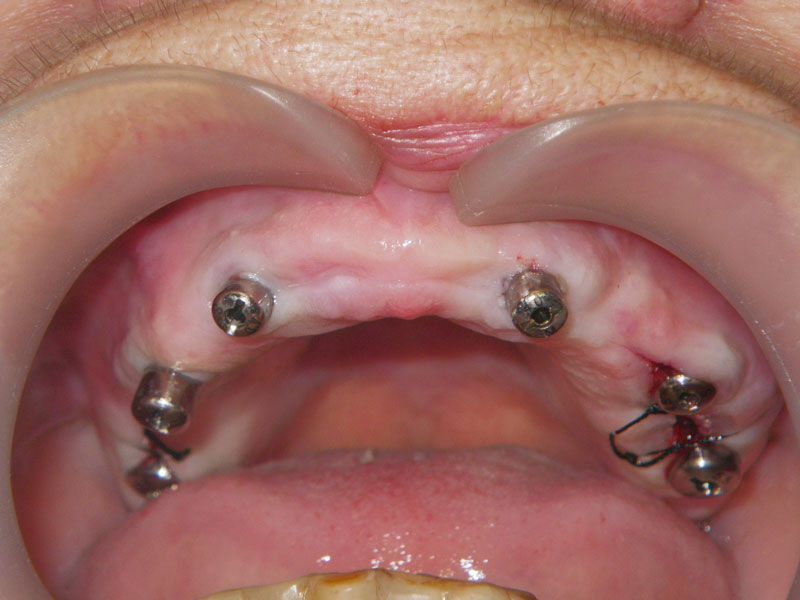

Через 10 недель, после 3D-моделирования и подробнейшего планирования, была проведена операция установки имплантов в позиции опорных зубов. Нужно отметить, что операция, несмотря на объем, была малоинвазивной: импланты были подобраны таким образом, что не потребовалось проводить обширных костных пластик.

Сразу после операции была проведена коррекция протеза и наша пациентка ушла домой с привычным к тому моменту собственным съемным протезом. Летние месяцы пролетели быстро, и уже через три месяца она обратилась в нашу клинику за контрольными снимками и окончательным протезированием.